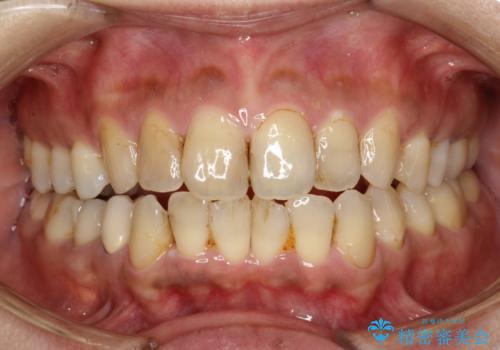

40代 男性 ホワイトニングで歯を白く

- 歯を白くしたいと来院された患者様です。

右上の前から2番目の歯は根管治療をされている歯で、1番前の歯は根管治療はされていないが変色している歯でした。

2番目の歯に対しては歯質が多く残っていたためウォーキングブリーチ(ホワイトニング)を行い、その他はレーザーホワイトニングを行いました。

今回の治療ではまず最初に右上の2番のウォーキングブリーチを行い、その後にレーザーホワイトニングを行い白くなるタイミングが一緒になるように配慮いたしました。

最初と比較し周囲の歯と変色した歯の調和を取ることができました。